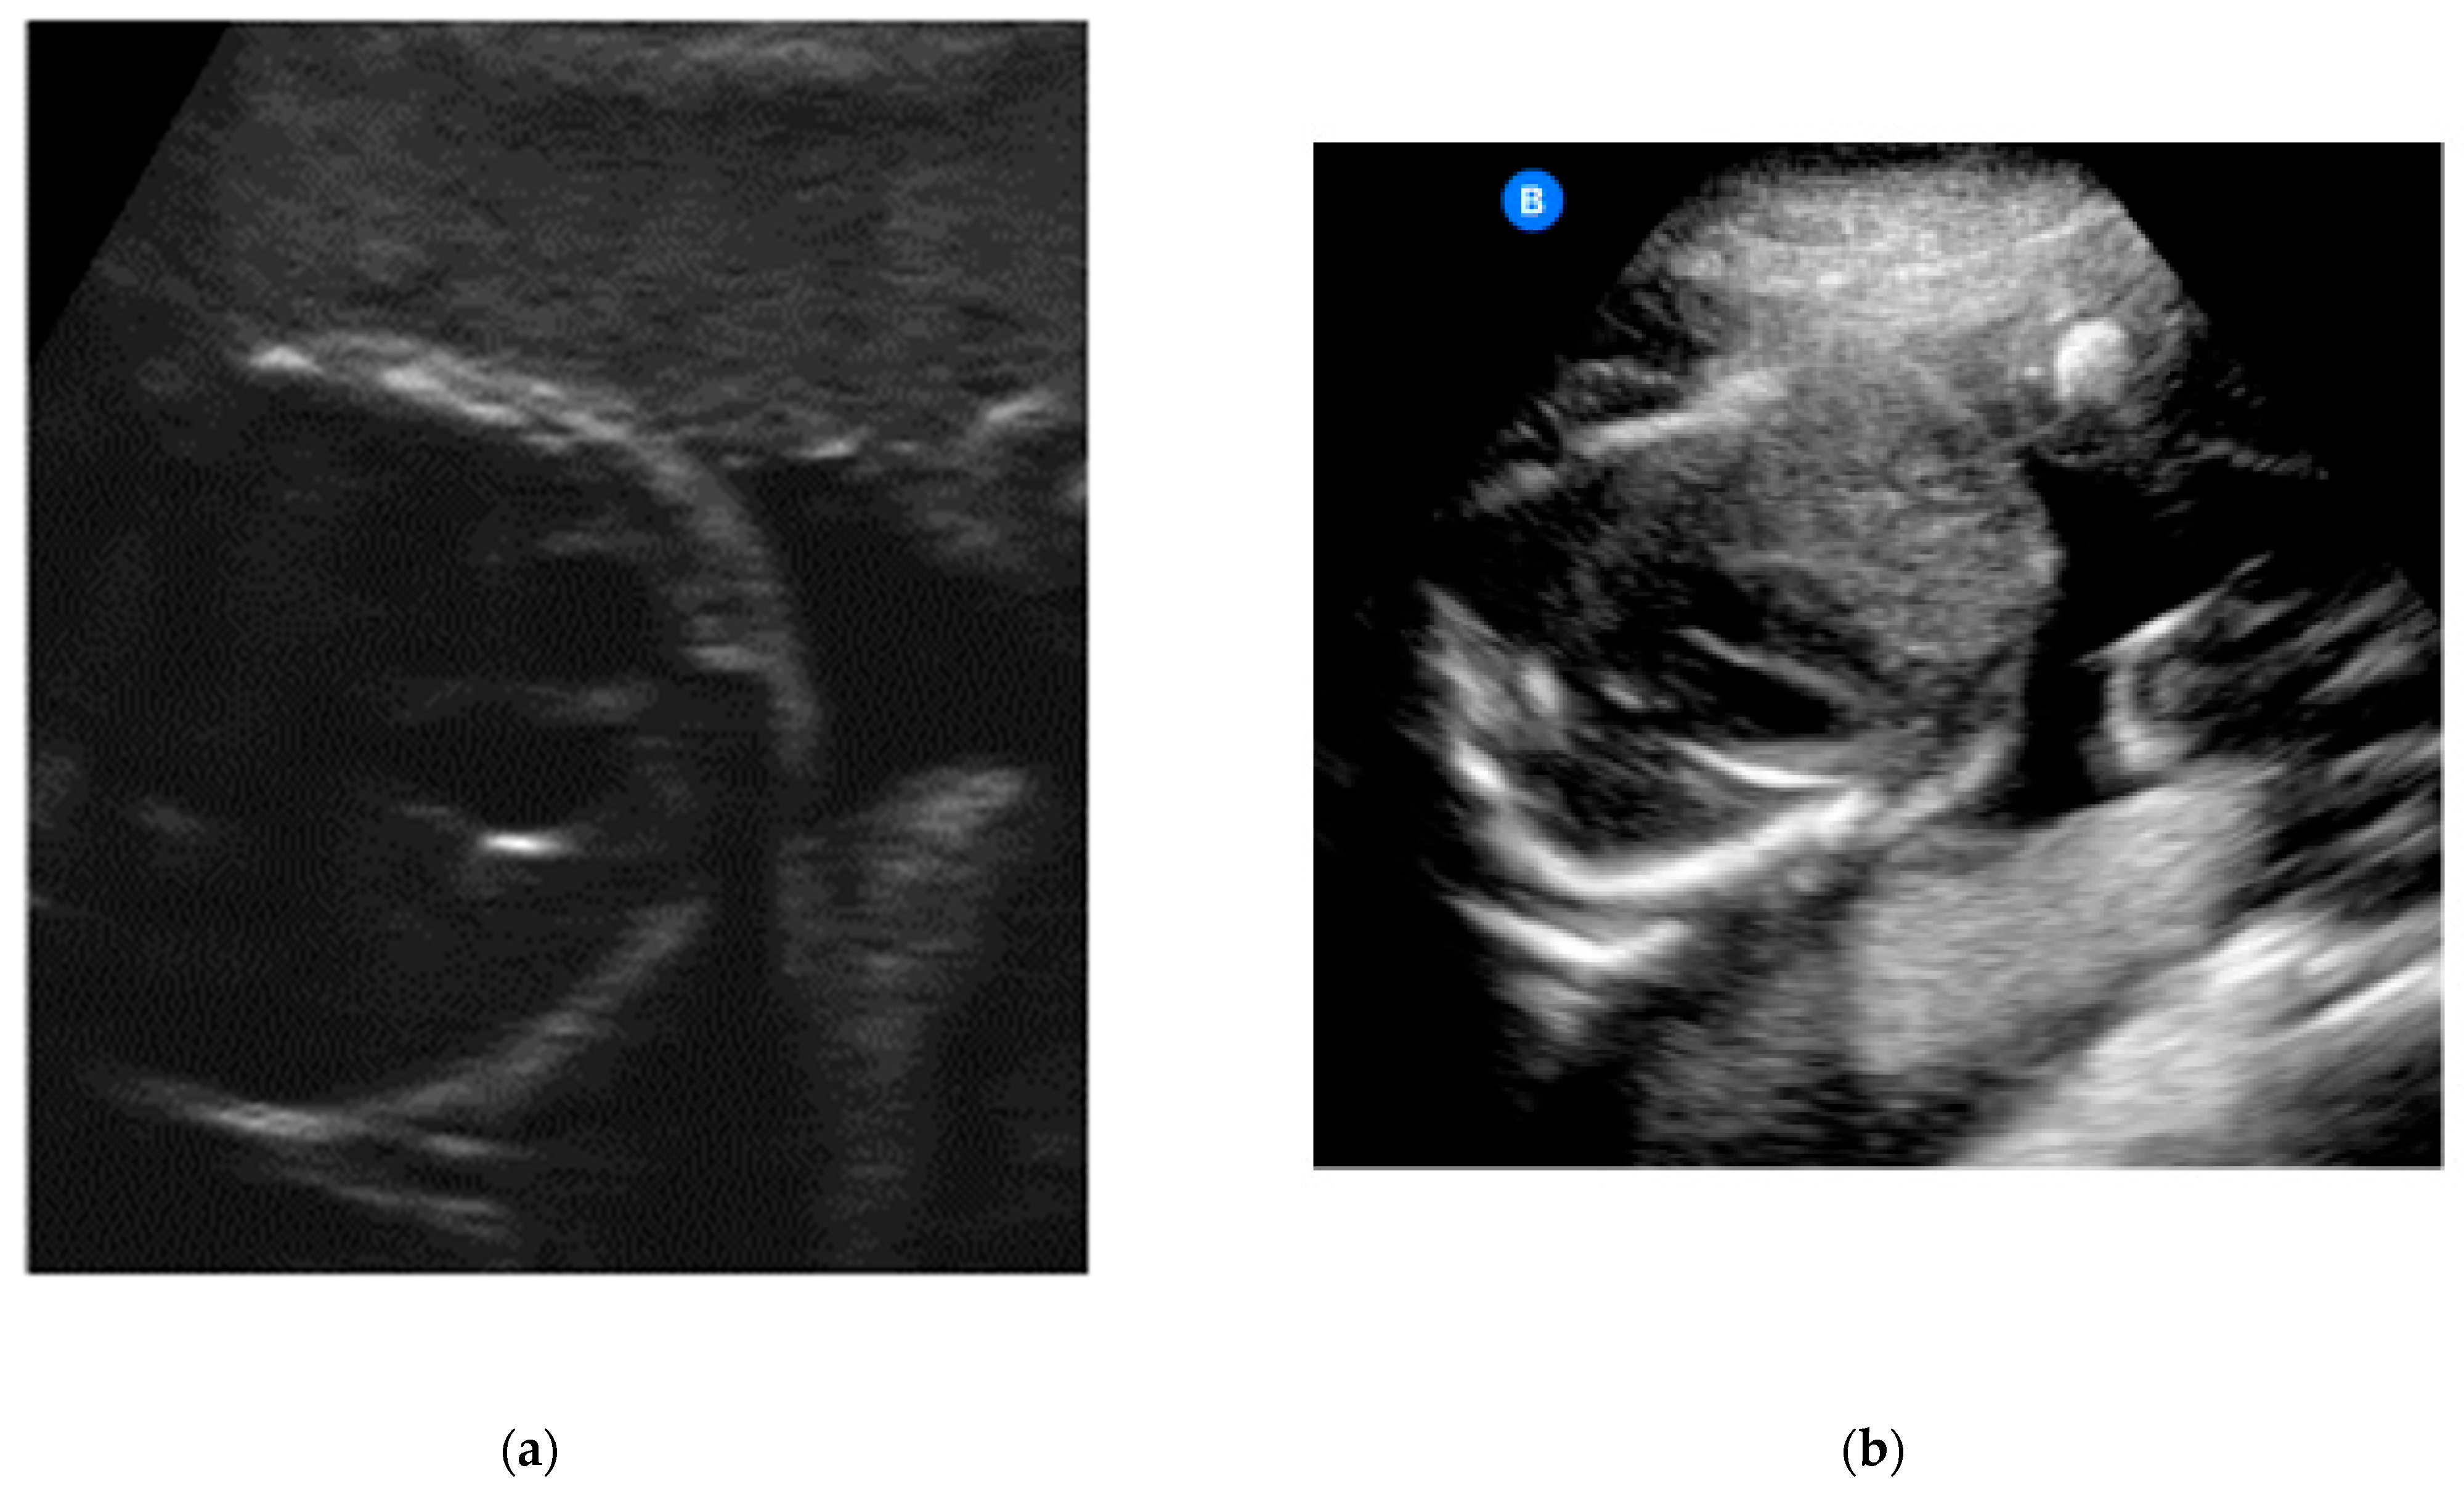

The heartbeat was correctly captured by more than half of the participants (n = 24, 52.2%; Table 3) (Figure 2a,b).

Figure 2.

(a) Example of an image obtained by a study participant in cohort A, showing the heartbeat (satisfactory presentation). (b) Example of an image obtained by a study participant in cohort B, showing the heartbeat (satisfactory presentation).

With regard to identifying the amniotic fluid during the 15-s video, 43 of the 46 participants (93.5%) managed to locate the amniotic fluid correctly in at least one of the four quadrants (Figure 3a,b). A total of 52.2% succeeded in locating the amniotic fluid in all four quadrants in the videos. In relation to capturing still images of the amniotic fluid, the rate of images with sufficient quality was lower than with the videos (80.4% with at least one adequate still image in the four quadrants and 43.5% with sufficient quality in all four quadrants).

Figure 3.

(a) Example of an image obtained by a study participant in cohort A, showing the amniotic fluid (satisfactory presentation). (b) Example of an image obtained by a study participant in cohort B, showing the amniotic fluid (satisfactory presentation).